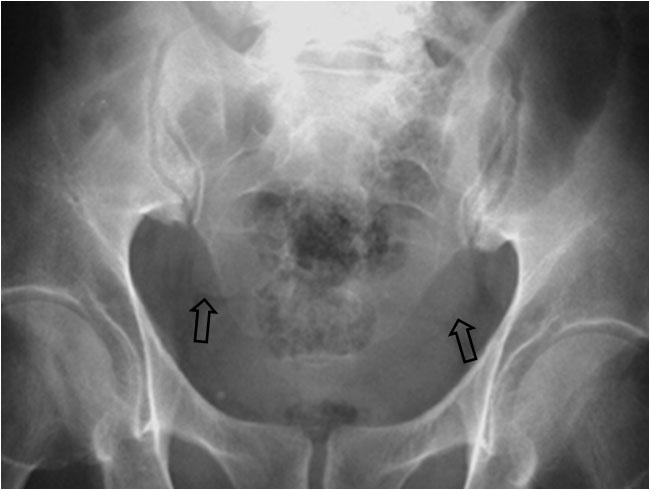

SIGNO DE LAS OREJAS DE PERRO

En un paciente que presente líquido libre en la cavidad peritoneal, al adoptar la posición de decúbito supino, ésta desciende por efecto de la gravedad hacia las porciones más bajas de la pelvis, acumulándose en las reflexiones pélvicas del peritoneo. Al llenarse los recesos pélvicos laterales a ambos lados de la vejiga urinaria, se forma una imagen densa simétrica que recuerda las orejas de un perro.

Imagen coronal de TC en otro paciente con ascitis rellenando los recesos pélvicos (flechas) que justifican la imagen de la radiografía.